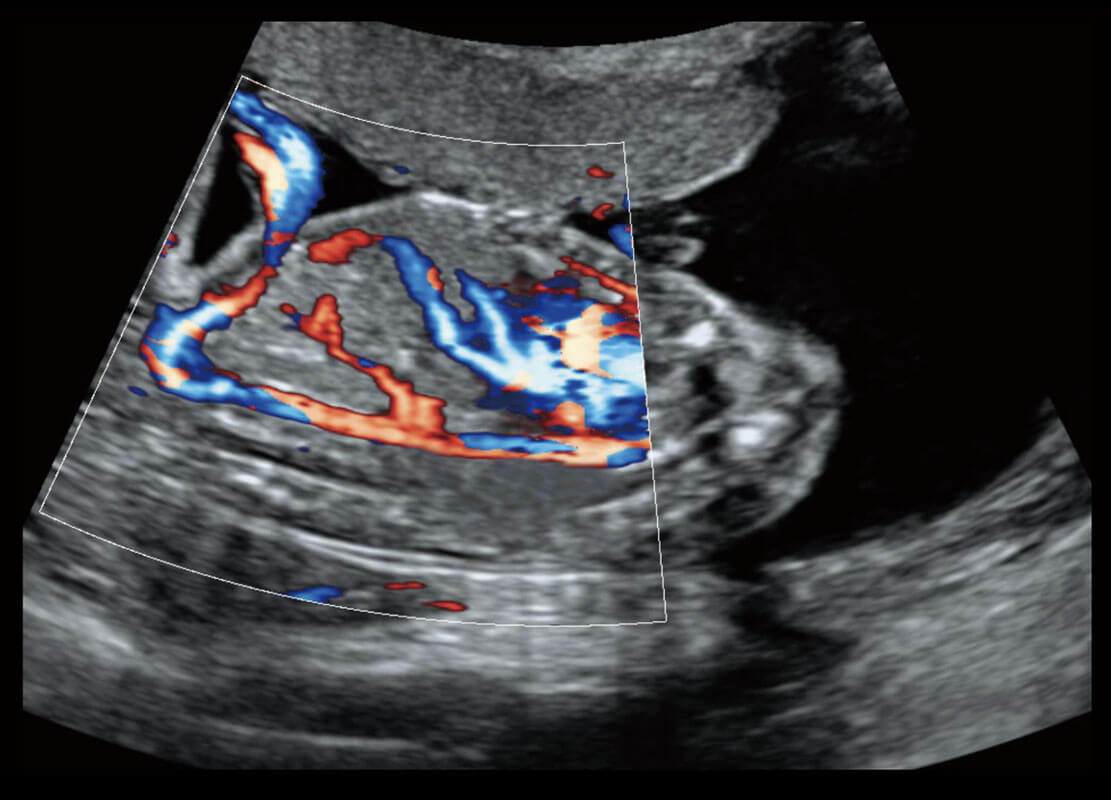

胎儿体循环

P60搭载一系列胎儿心脏成像技术,实现精细的胎儿心脏评估。

四腔心血流